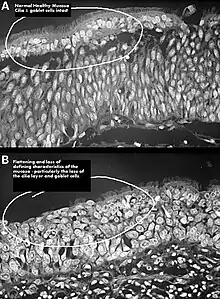

![]() | |

Altered nasal anatomy after bilateral subtotal inferior turbinectomy, the removal of most turbinate tissue. | |